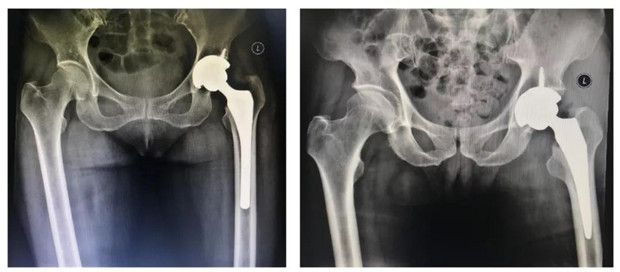

2节段腰椎间盘突出伴椎管狭窄钉棒系统Cage植骨内固定术